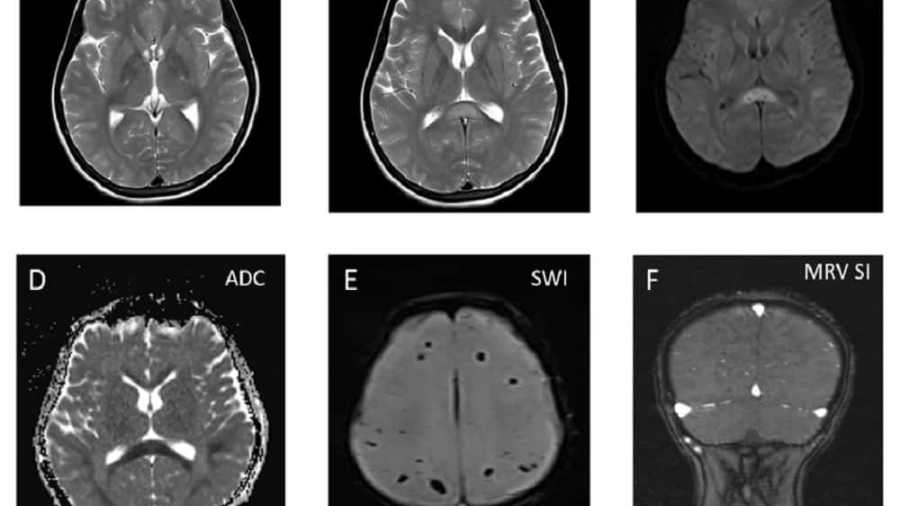

56 female

Acute onset severe headache – holocranial- thunderclap type while bathing with no postural variation. Recurrent vomiting and neck stiffness.

Prior H/o disabling migraine attacks